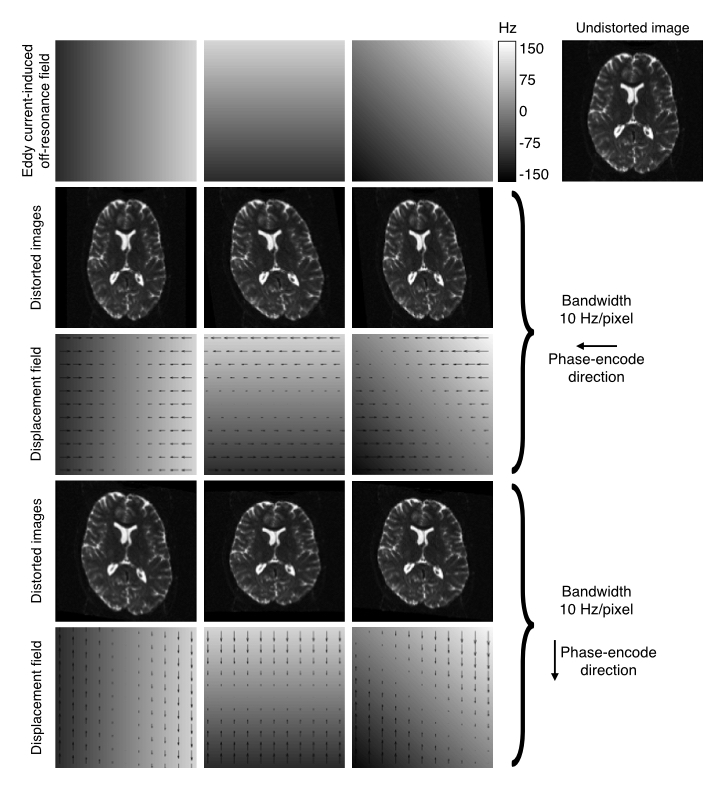

The seminal paper by Jezzard el al. describes the distortions as a \(yx\)-shear, a \(y\)-zoom and a \(z\)-translation. This was predicated on the EC-induced field being a linear combination of \(x\), \(y\) and \(z\) linear gradients, the PE-direction being along \(y\) and on considering it as a 2D problem. In the figure below is a more general explanantion for how the EC-induced fields translate into distortions.

| Explanation of how EC-fields translate into distortions. |

|---|

![]() |

| The top row shows EC-fields linear in the $x$, $y$ and $xy$-directions in columns 1-3 respectively. The fourth column shows an undistorted image. Row two shows the resulting distorted images for data acquired with the phase-encoding in the $y$-direction, and row three shows the corresponding displacement fields. Rows four and five shows the same for the case where the phase-encoding is in the $y$-direction. |

The fields and distortions in the figure above still assume that the EC-fields are "perfect" linear combinations of linear gradients. However, that is not a given and there is ample evidence that this is not generally true (I would personally go as far as to say the it is generally not true). When validating eddy on the HCP data we found strong evidence both for quadratic and cubic terms, even though the cubic terms where sufficiently small to safely ignore even though they could be reliably detected.